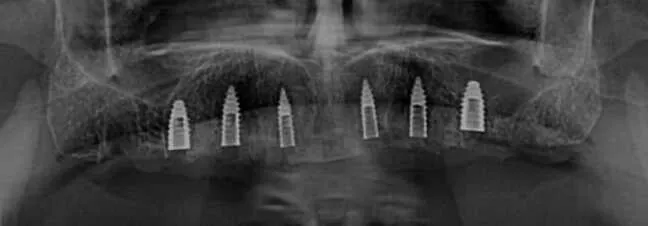

- Toma de tomografía dental

¿Debo realizarme una tomografía?

Si, una tomografía es indispensable al inicio de todo tratamiento con base en implantes dentales. Solo con ella se puede determinar el estado actual del paciente y planificar los implantes a instalar.